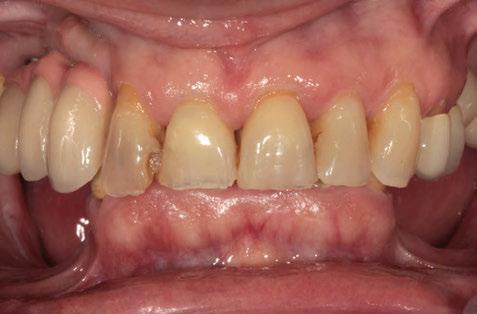

Figuras 4 y 5. Imagen intraoral y de sonrisa de la paciente en la primera visita. En ellas observamos el colapso de la mordida a nivel anterior, con una sobremordida del 100%.

Figuras 6 y 7. Al retirar las prótesis removibles observamos en el arco inferior una gran reabsorción ósea del sector posterior, con elevación del suelo de la boca y la invasión de los tejidos blandos, lo que nos hace suponer que existe una gran atrofia ósea asociada.

Figuras 18-21. Imágenes iniciales y finales de la paciente a los dos años de seguimiento donde observamos el cambio de la sonrisa y la recuperación de la dimensión vertical realizada con la rehabilitación sobre implantes y la confección de nuevas prótesis sobre implantes en el primer cuadrante y facetas en los sectores anteriores superiores e inferiores.